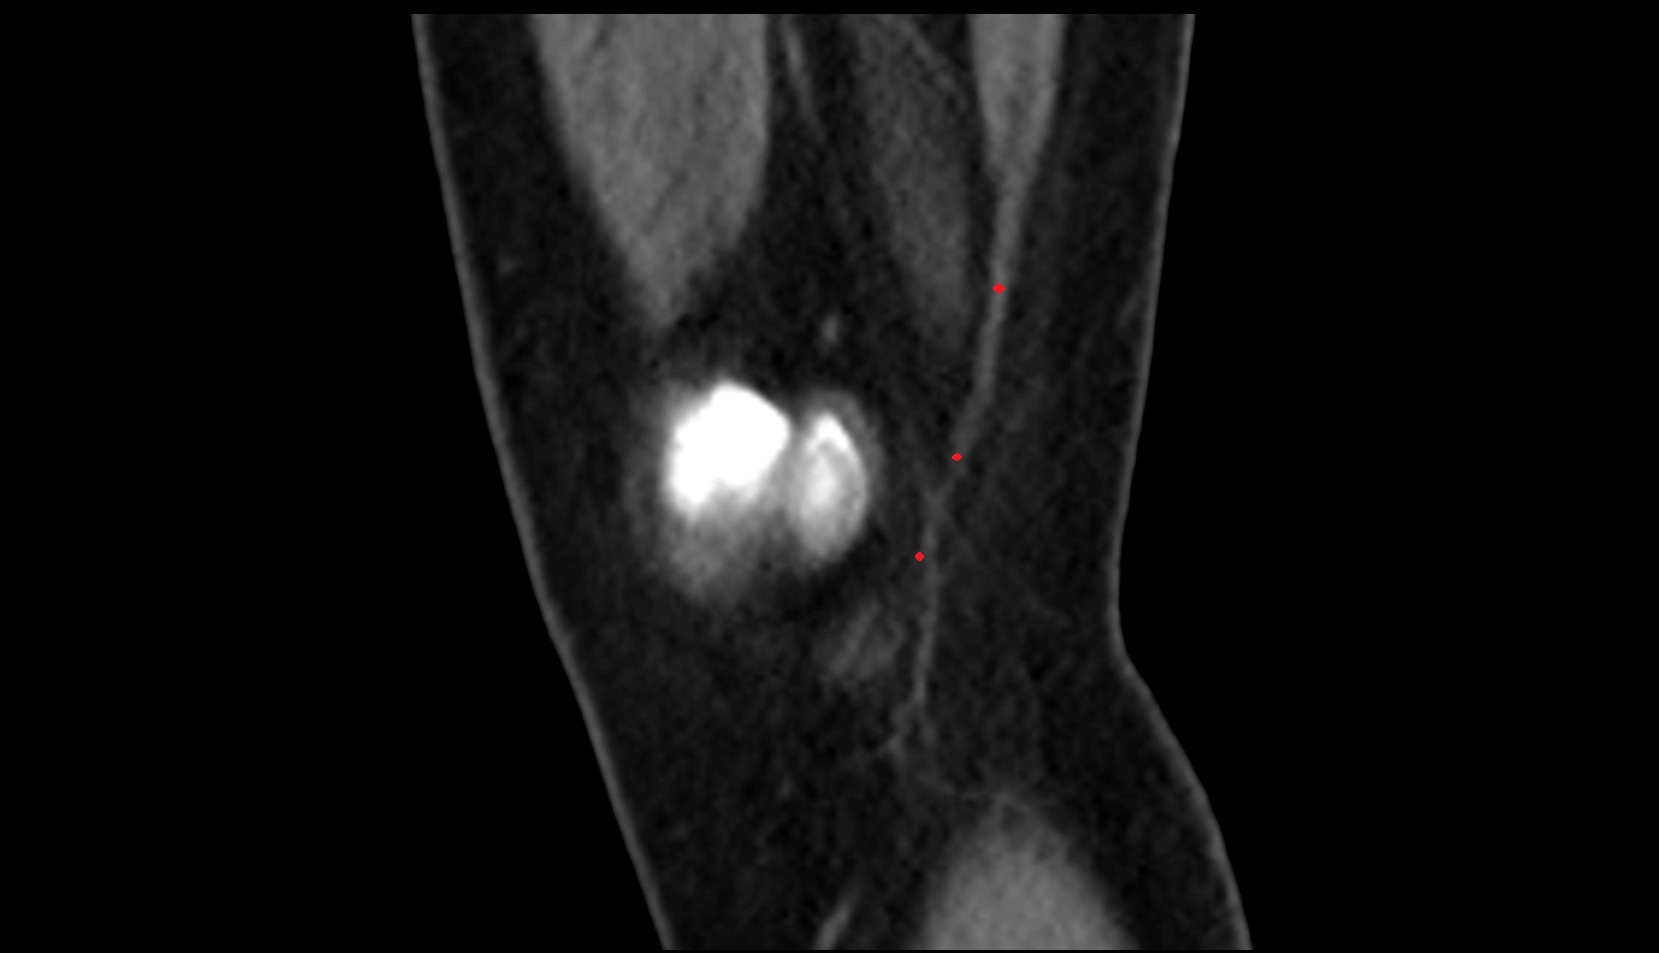

- Popliteal artery

- Popliteal vein

- Lateral condyle of femur

- Medial condyle of femur